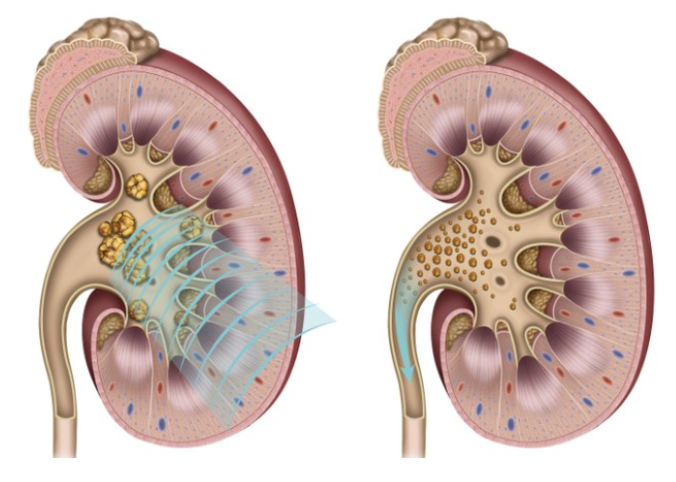

3) 체외충격파쇄석술

체외충격파쇄석술은 수술 조작 없이 몸 밖에서 충격파를 발사하여 결석을 잘게 분쇄하여 자연 배출이 되도록 유도하는 치료법으로 쇄석술 후에 분쇄된 결석은 대개 2주 이내에 자연적으로 배출되며 3개월 후 시술의 성공 여부를 판정하게 됩니다.